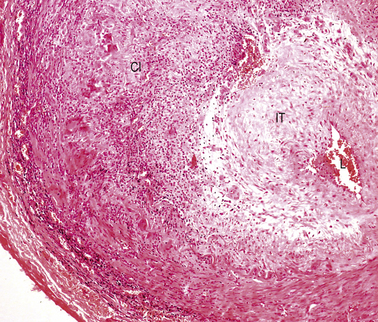

In florid clinical cases the superficial temporal artery is hard, tender and pulseless, and the patient complains of a severe headache. The ESR is usually high, generally above 50 mm/h. Microscopically there is marked intimal thickening and oedema, and a dense, sometimes granulomatous, chronic inflammatory and giant cell reaction with phagocytosis of fragmented elastic fibres (Fig. 13.16). The clinical diagnosis can often be confirmed by biopsy, but this is not always positive; focal involvement of the superficial temporal artery is the probable reason for these negative biopsies.

Fig. 13.16 Cranial arteritis. This biopsy of a superficial temporal artery shows marked intimal thickening (IT) and a dense mononuclear and giant cell infiltrate (CI). The lumen is restricted to a tiny slit (L).

The cause of cranial arteritis is unknown. There is little evidence that it is immunological in origin. In up to 50% of cases it is associated with a polymyalgia rheumatica-like illness. Almost all cases of cranial arteritis respond well to steroid therapy and, in severe cases, prompt treatment can prevent blindness.